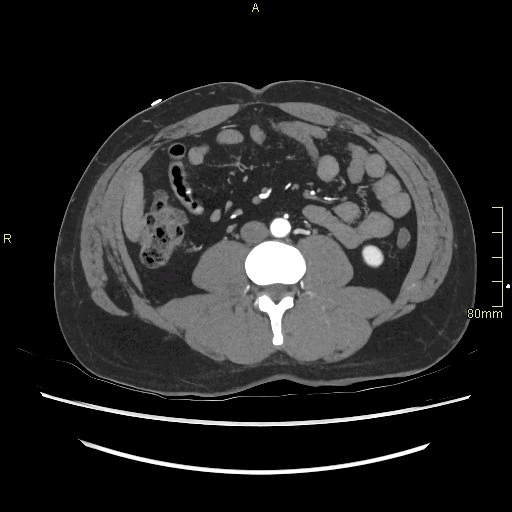

CT Angiography Pelvis - Maximum Intensity Projection (axial)